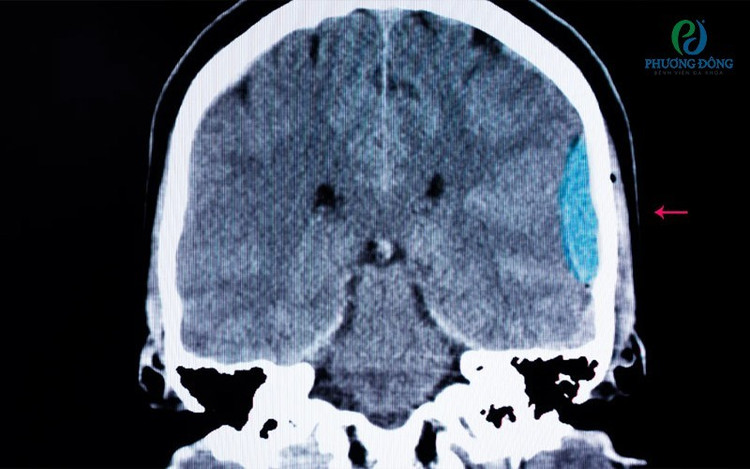

Tuy nhiên, kết quả chẩn đoán hình ảnh cho thấy bệnh nhân bị tụ máu nhu mô não vùng thái dương trái, kèm tràn máu não thất bên trái và não thất III. Trước tình trạng nguy hiểm, bệnh nhân được chỉ định nhập viện cấp cứu, điều trị theo chuyên khoa thần kinh.

6h sáng bệnh nhân vẫn đi thể dục, sau 1 tiếng đau đầu đột ngột phát hiện tụ máu não (Ảnh: BV 19-8).